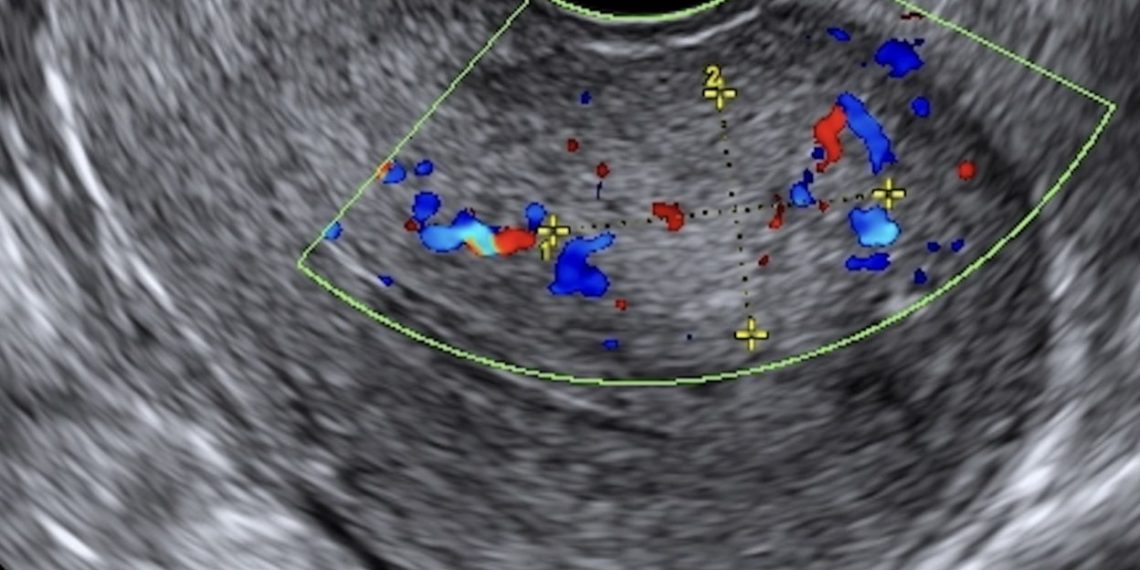

Guida al Counseling di Giugno: adenomiosi

vi presentiamo la guida al counseling di Giugno relativa alla diagnosi e alla gestione dell’adenomiosi. Potrete scaricarla cliccando sul link.